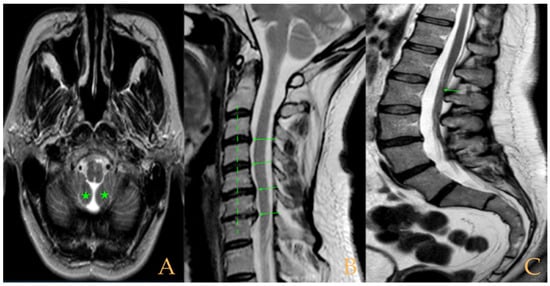

The cranio-vertebral magnetic resonance showed empty sella turcica, discrete descent of the cerebellar tonsils, C4-C5-C6 disc protrusions and cervical hypermobility with a tense medullary aspect in flexion in the incorporated dynamic test, and conus medullaris at the height of the TH12-L1 disc (Figure 3). No scoliosis was observed in the full-spine X-rays. The patient was not operated on. Cases 8 and 9 were very similar and involved previously diagnosed cranio-cervical and atlantoaxial instability. The patient used a cervical collar, as she was afraid that she might suffer spontaneous cervical luxation.

Figure 3. Imaging of patient 3. A: Empty sella turcica (arrow); B: discrete descent of the cerebellar tonsils (arrow); C: C4C5 and C5C6 disc protrusions (arrows); and D: tense spinal cord in cervical flexion (interrupted line).